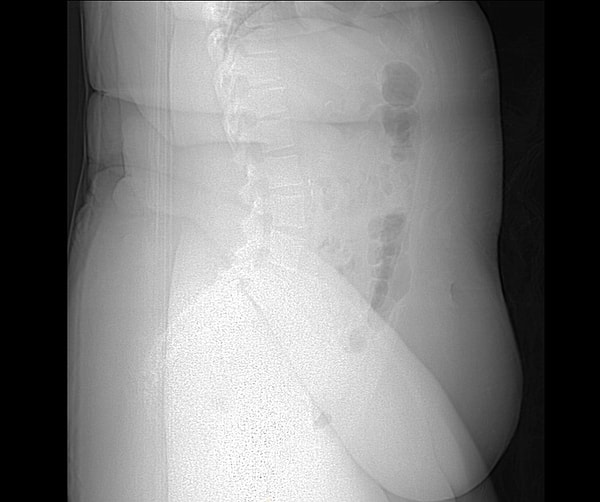

3. 37 haftalık hamile bir kadının tomografisi: